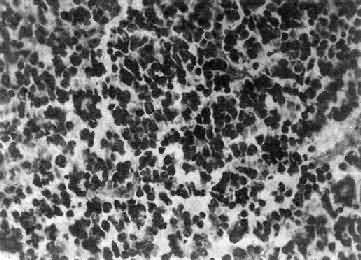

图16-25 室管膜瘤 瘤细胞为圆形或卵圆形,核染色质丰富,胞浆少,可见有细长的胞浆突起与血管相连,呈放射关,形成假菊形团 (二)髓母细胞瘤 髓母细胞瘤(medulloblastoma)好发于儿童,仅次于星形胶质细胞瘤而占第2位,其发生率占儿童颅内肿瘤的25%,发病年龄75%为15岁以下,偶见于成人,男性较女性为多(2~3:1)。 本瘤来源于小脑蚓部的原始神经上皮细胞或小脑皮质的胚胎性外颗粒层细胞,故本瘤主要见于小脑,在儿童多发生于小脑蚓部,在成人则多见于小脑半球。 肉眼观,瘤组织呈鱼肉状,色灰红。镜下,肿瘤由圆形、椭圆形或胡萝卜形细胞构成,胞核着色深,胞浆少而边界不清楚,有多少不等的核分裂像。细胞密集,间质中有纤细的纤维,血管不多。瘤细胞环绕一个嗜银性纤细的神经纤维中心作放射状排列形成典型的菊形团(图16-26),这对髓母细胞瘤的病理诊断有一定的意义。瘤细胞具有向神经元及神经胶质双向分化的潜能,既能向神经母细胞、节神经细胞分化,也能向胶质母细胞、星形胶质细胞分化。如瘤细胞侵入软脑膜,可在蛛网膜下腔脑脊液中广泛播散转移。

图16-26 髓母细胞瘤 瘤细胞较小,着色深,密集排列,有菊形团形成 髓母细胞瘤恶性程度高,预后差。 (三)脑膜瘤 脑膜瘤(meningioma)可来源于脑膜的各组成成分如蛛网膜细胞,纤维母细胞或血管,其中多数来源于蛛网膜颗粒中的蛛网膜细胞。本瘤大多生长缓慢,良性类型可完全无症状,在70岁以上老人的尸检中,发现无症状的脑膜瘤不在少数,无症状脑膜瘤占颅内肿瘤的14%。脑膜瘤患者多为40~50岁中年人,女性较男性多。 肿瘤的好发部位与蛛网膜颗粒所在部位相同,常见于上矢状窦旁大脑镰两侧,蝶骨嵴,嗅沟,小脑脑桥角;在脊髓则以胸段为多见,一般颅内脑膜瘤较脊髓脑膜瘤多2倍。 肉眼观,肿瘤呈球形,分叶状或不规则形,质实或硬,边界清楚,周围脑组织受压成凹陷切迹(图16-27)。少数肿瘤呈斑块状覆盖较广泛区域,甚至整个脑半球,称为斑块型脑膜瘤。肿瘤质地硬,切面灰白色,呈颗粒状、条索旋涡状,有的质地似砂砾样,乃由于有多量砂粒体存在。